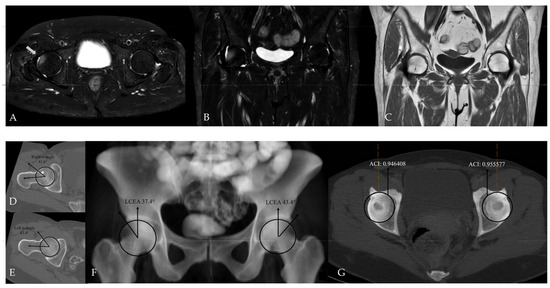

Figure 8.

Hip MRI demonstrates bilateral posterolateral femoral head bone marrow edema on (A) axial (white arrows) and (B) coronal fat-suppressed T2-weighted images, more pronounced on the right, with associated right hip joint effusion. (C) Coronal T1-weighted image shows no structural abnormality. (D,E) CT shows normal alpha angle measurements, and (F) LCEA values are within normal limits. (G) However, the ACI exceeds the 0.93 cut-off value on the left, while CT–MIP images demonstrate posterior acetabular rim overcoverage on the right without marked posterior wall lateralization.